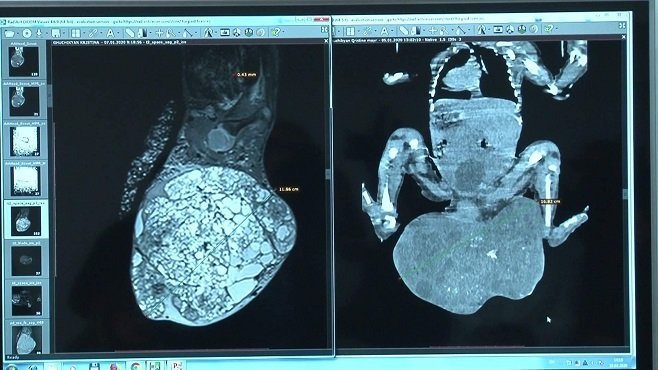

Հայ բժիշկները կատարել են հազվագյուտ վիրահատություն, որի շնորհիվ հաջողվել է փրկել նորածին երեխայի կյանքը։ Փոքրիկը ծնվել է 9 ամսականում 2,55 կգ քաշով, որից 1,2 կգ-ը եղել է բնածին ուռուցքը՝ տերատոման, որը տեղակայված էր կոնքային հատվածում։

Ուռուցքը հայտնաբերվել է հղիության ուշ շրջանում, ինչի շնորհիվ հնարավոր է եղել կանխատեսել հնարավոր բարդությունները, նշանակվել է կեսարյան հատում։ Վիրահատությունը կատարվել է «Սուրբ Աստվածամայր» ԲԿ-ում՝ հունվարի 8-ին, տեւել է 3,5 ժամ։

ԲԿ-ի վերակենդանացման բաժնի վարիչ Չոբանյանի խոսքով՝ վիրահատությունը բացառիկ էր առաջին հերթին տերատոմայի չափերով․ «Տերատոմայի ծավալը շատ մեծ էր՝ երեխայի քաշի 1/3-ի չափով, կար ներանոթային մակարդման համախտանիշ, այսինքն՝ կային տրոմբիկներ այդ գոյացության մեջ, այն շատ արյունատար էր, երեխայի հեմոգլոբինն էր իջնում, կարիք ուներ արյան փոխներարկման։ Հետվիրահատական առաջին օրերին ընդհանուր ծանր վիճակ էր, բայց բարեհաջոց հաղթահարվեց։ Երեխան ոտքերը շարժում է, կոնքային խանգարումներ չունի, մնացած օրգանները նորմայի մեջ են»։